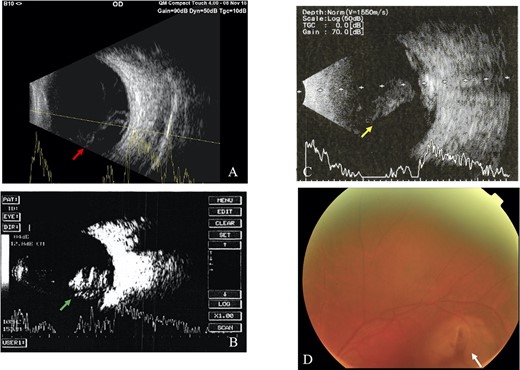

All IOFBs were successfully identified using slit-lamp biomicroscopy, fundus examination, B-scan ultrasonography, plain orbital X-ray, and viewed intraoperatively. Most foreign bodies were intravitreal (four patients, Fig. 1), followed by intraretinal (two patients, Fig. 2), intralenticular (two patients, Fig. 3) and intracorneal (one patient, Fig. 4).

Intravitreal foreign body; (A) B-scan ultrasound revealed vitreous hemorrhage with retinal detachment in Case 6 (red arrow), (B) vitreous hemorrhage in Case 7 (green arrow), (C) vitreous hemorrhage with retinal detachment of the LE in Case 9 (yellow arrow), (D) fundus examination showed hazy vitreous with a retinal tear (white arrow) near superior temporal arcade of the retinal artery (Case 9).